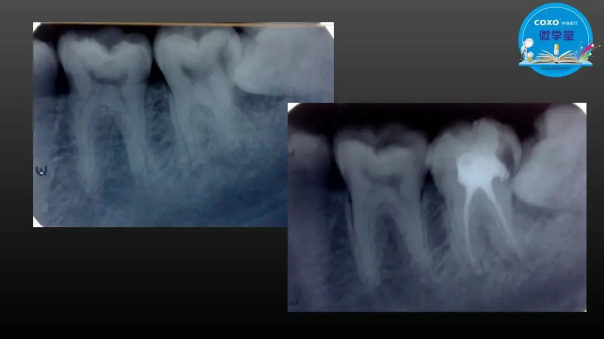

主任醫(yī)師,牙體牙髓副主任, 廣東省口腔醫(yī)院牙體牙髓科 主任醫(yī)師。2003年碩士研究生畢業(yè),研究方向為牙體牙髓病學,擅長于牙體牙髓病的診斷、齲齒、牙髓炎、根尖周病的治療以及前牙美容修復。